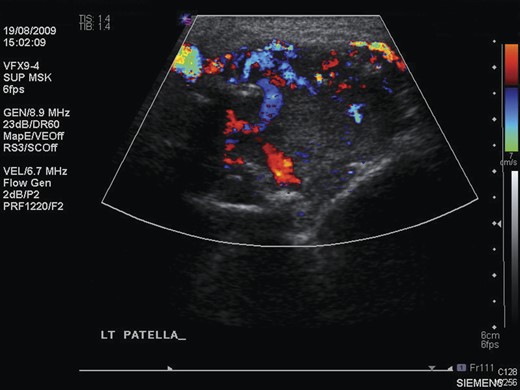

Ultrasound scan of the left patella, showing extensive neovascularization and increased flow within the lesion.